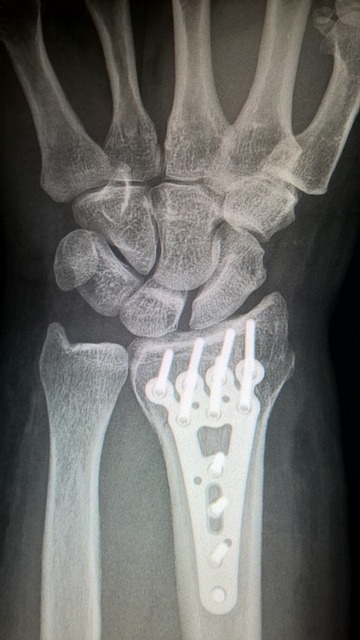

진단 이미징의 역할

진단 이미징은 손목의 내부 구조를 시각적으로 확인할 수 있는 중요한 도구이다. 엑스레이는 뼈의 골절 여부를 확인하는 데 유용하며, MRI는 연부 조직의 손상이나 염증을 평가하는 데 도움을 준다. 이러한 검사를 통해 손목 통증의 원인을 보다 명확히 할 수 있다.